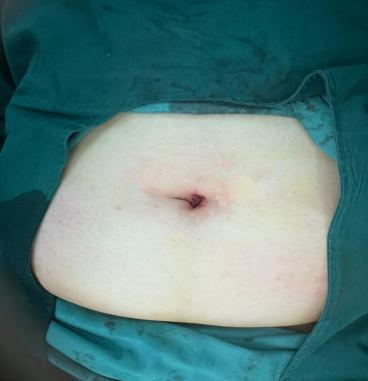

单孔腹腔镜较普通的多孔腹腔镜在腹部的伤口更少更微创,患者痛苦更少恢复更快,腹部几乎看不到伤口,满足了女性最大的爱美需求,让广大爱美女性患者尽情绽放“她”美丽。